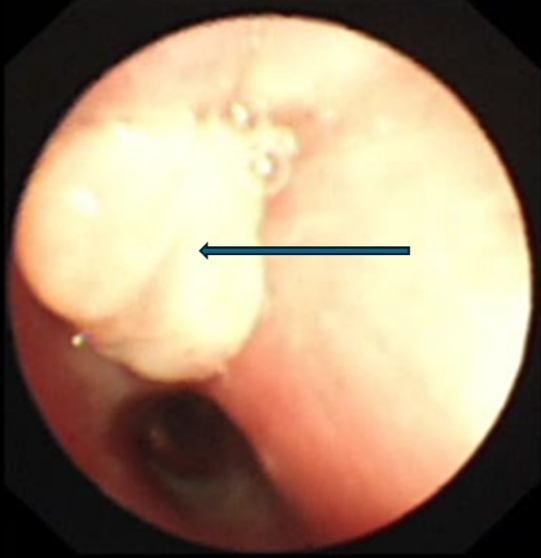

支气管镜下的景象触目惊心:乐乐右主支气管管腔内满是脓性分泌物,且增生的肉芽组织堵塞了右上叶支气管开口。在更深处,一个看似尖锐异物死死堵住了右中间支气管管腔。

支气管镜检查显示右上叶支气管肉芽增生,完全堵塞开口

在呼吸科支气管镜室,张东伟主治医师和叶颖龙主管护师紧密配合,小心清理了分泌物,最终用异物钳成功钳取出异物——竟是一颗草莓味糖果的包装纸!展开测量,长度接近3.5厘米。